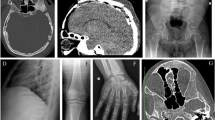

Transmembrane protein 53 (TMEM53) is an outer nuclear membrane protein that plays a crucial role in maintaining skeletal homeostasis. Pathogenic variants in TMEM53 have been identified as the genetic cause of craniotubular dysplasia, Ikegawa type (CTDI), a rare form of sclerosing bone dysplasia characterized by skull hyperostosis, cranial deformities, and increased bone density. To date, the causal association of bi-allelic pathogenic variants of TMEM53 in CTDI has been identified in 14 patients from eight unrelated families. Mechanistically, TMEM53 negatively regulates BMP–SMAD signaling by restricting the nuclear import of phosphorylated SMAD1/5/9, thereby modulating osteoblast differentiation and bone formation. This review summarizes the current understanding of TMEM53 function and the consequences of its deficiency. We aim to clarify genotype-phenotype correlations, outline therapeutic prospects for CTDI, and explore the distinct mechanisms underlying cranial and tubular bone formation.